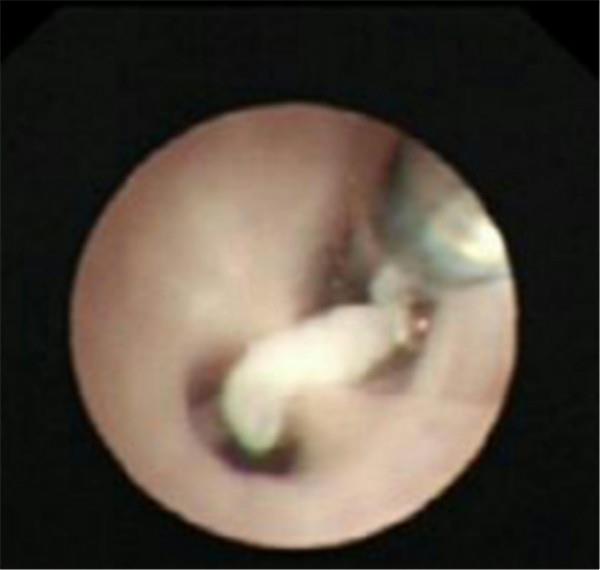

检查中气道内情景

呛入气道的瓜子